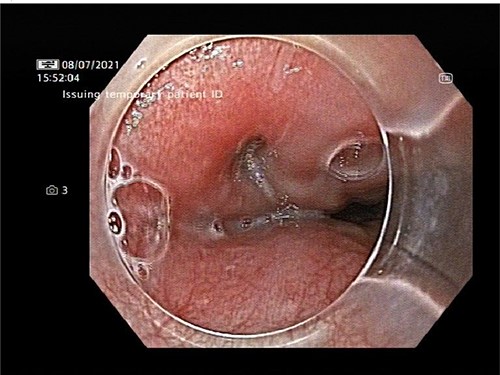

An OPF was confirmed on chest CT with water-soluble oral contrast. Endoscopy demonstrated three mucosal defects 31 cm from the incisors (Fig. 3). A fully-covered WallFlex stent (23 × 15 mm, Boston Scientific) was positioned to cover the OPF. The stent was secured proximally to the oesophageal mucosa using resolution clips and distally to the stomach using a 3–0 PDS trans-gastric suture placed laparoscopically. The patient improved and it was decided not to proceed with pericardial drainage.

Upper gastrointestinal endoscopy demonstrated three mucosal defects 31 cm from the incisors.